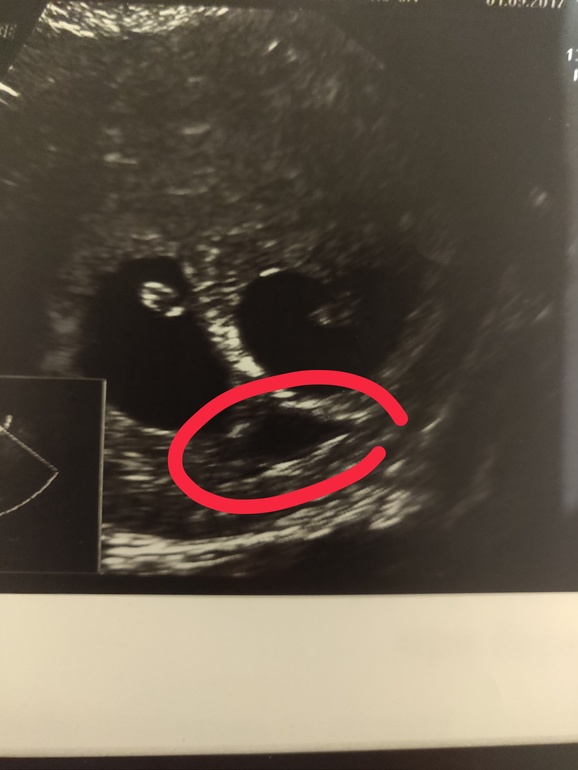

Гематома между плодными яйцами:

Как правило они не круглые